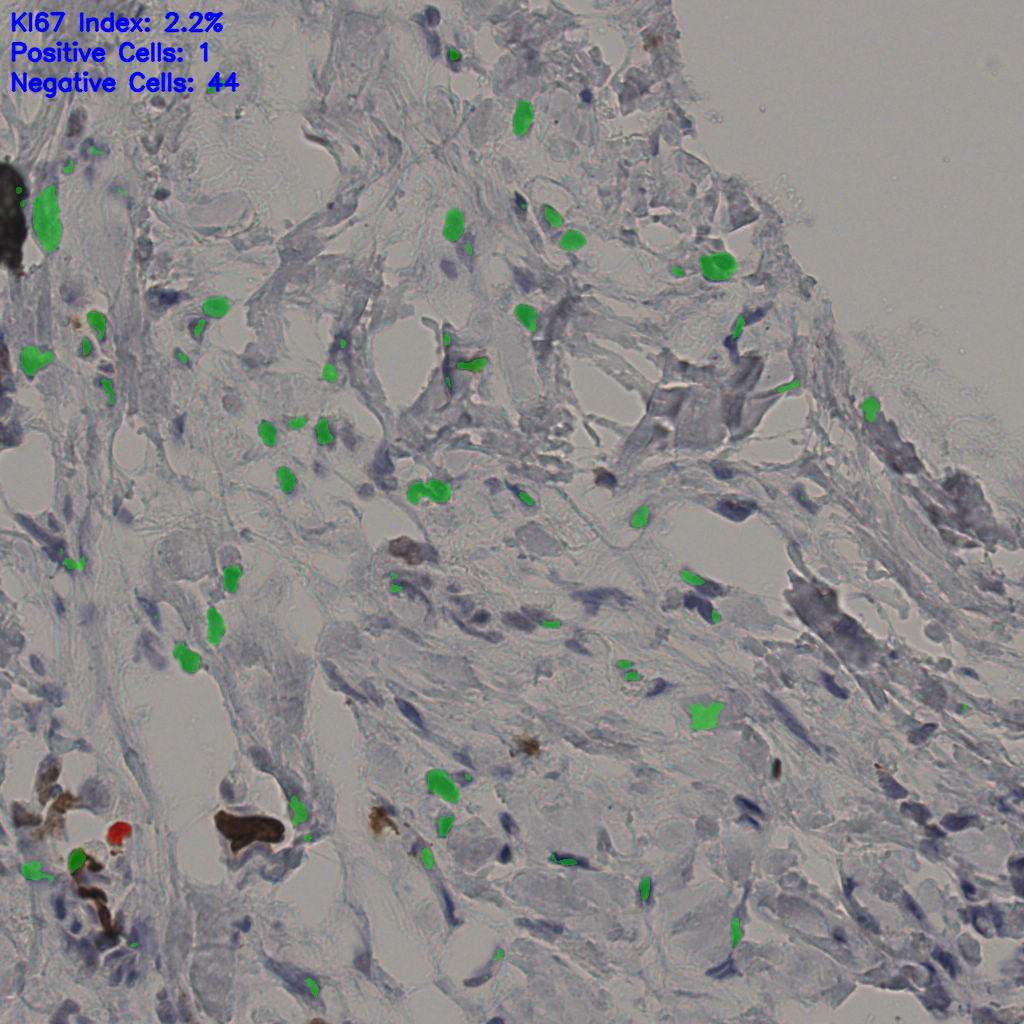

Ki67 指数

5.31%

阴 19502

阳 1093

切片统计

总切片

2970

有效

554

已标记

有效率

19%